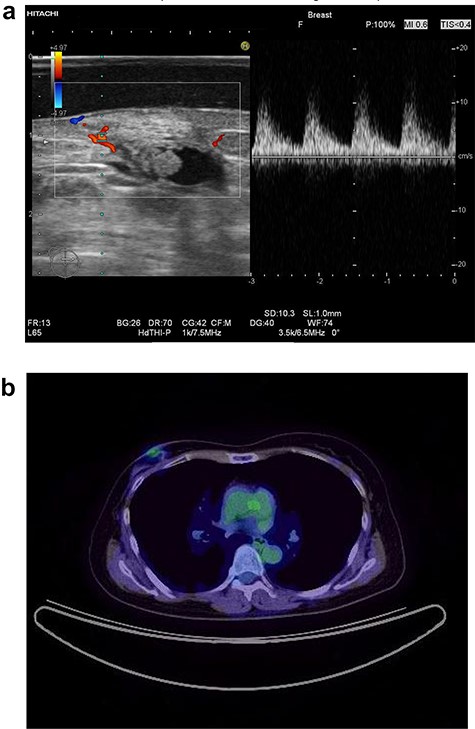

In 2014, a right breast tumor was located at the site of the surgical scar with slight erythema. Ultrasound revealed a hypoechoic mass with an irregular shape, indicating possible recurrence of breast cancer (Fig. 1a). Positron emission tomography–computed tomography (PET-CT) also suggested a right breast tumor with a relatively high standardized uptake value (SUV) and no distant metastasis (Fig. 1b). She underwent tumorectomy for both tumor removal and to obtain a pathological diagnosis, since she was afraid of false negative results with core needle biopsy (CNB). Pathological finding was a xanthogranulomatous lesion with cystic changes and dense sclerosis without any evidence of malignancy. There was no recurrence after surgery.

Ultrasound of the right breast in case 1 revealed a mass-like lesion 16.6 × 10.0 × 4.9 mm (a), and PET-CT showed that the right breast mass had an SUV max of 2.7 (b).